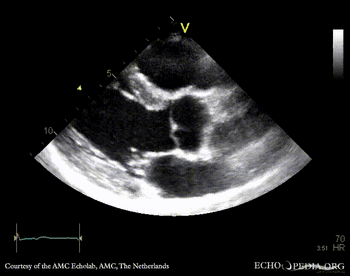

PSAX: bicuspid aortic valve with raphe PSAX: Color Doppler, mild aortic regurgitation